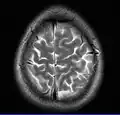

Normal axial T2-weighted MR image of the brain -